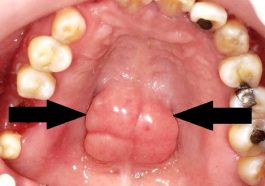

Torus Rongga Mulut: Sering Dikira Keganasan, Padahal Jinak

Lee Gay Lord - Torus rongga mulut adalah benjolan keras yang terkadang muncul di dalam rongga mulut dan sering menimbulkan…